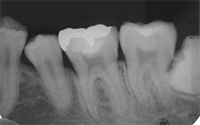

レントゲン撮影

歯科治療において必要不可欠な資料です。

[パノラマ]           [デンタル]